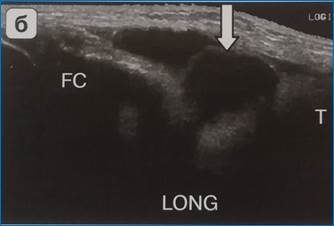

Бурсит сухожилий так называемой «гусиной лапки» по медиальной поверхности коленного сустава (рис. 7 а,б).

Рис. 7 б. Бурсит сухожилий так называемой «гусиной лапки» (ультразвуковая картина)